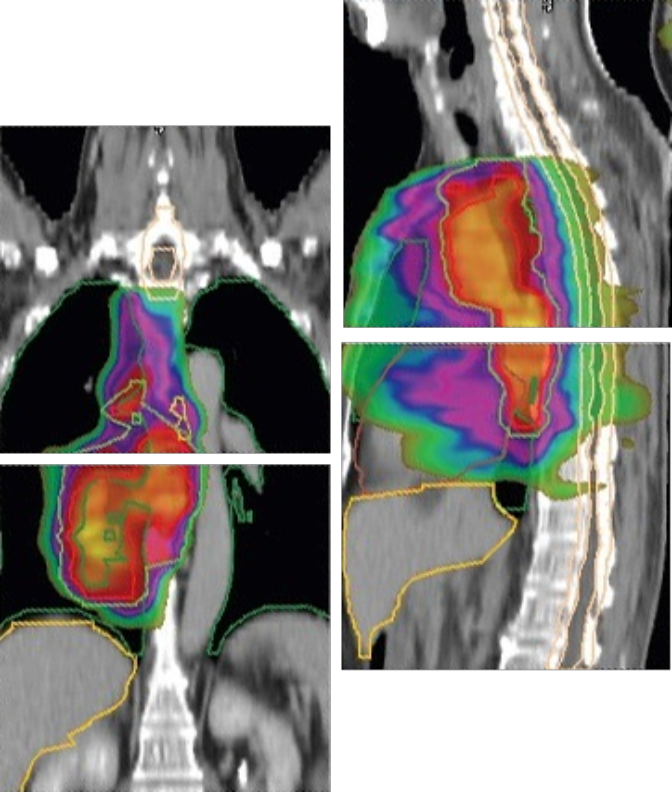

This Plan represents a cutting-edge approach to precision cancer treatment, integrating advanced imaging, adaptive planning, and novel delivery techniques to optimize patient outcomes.